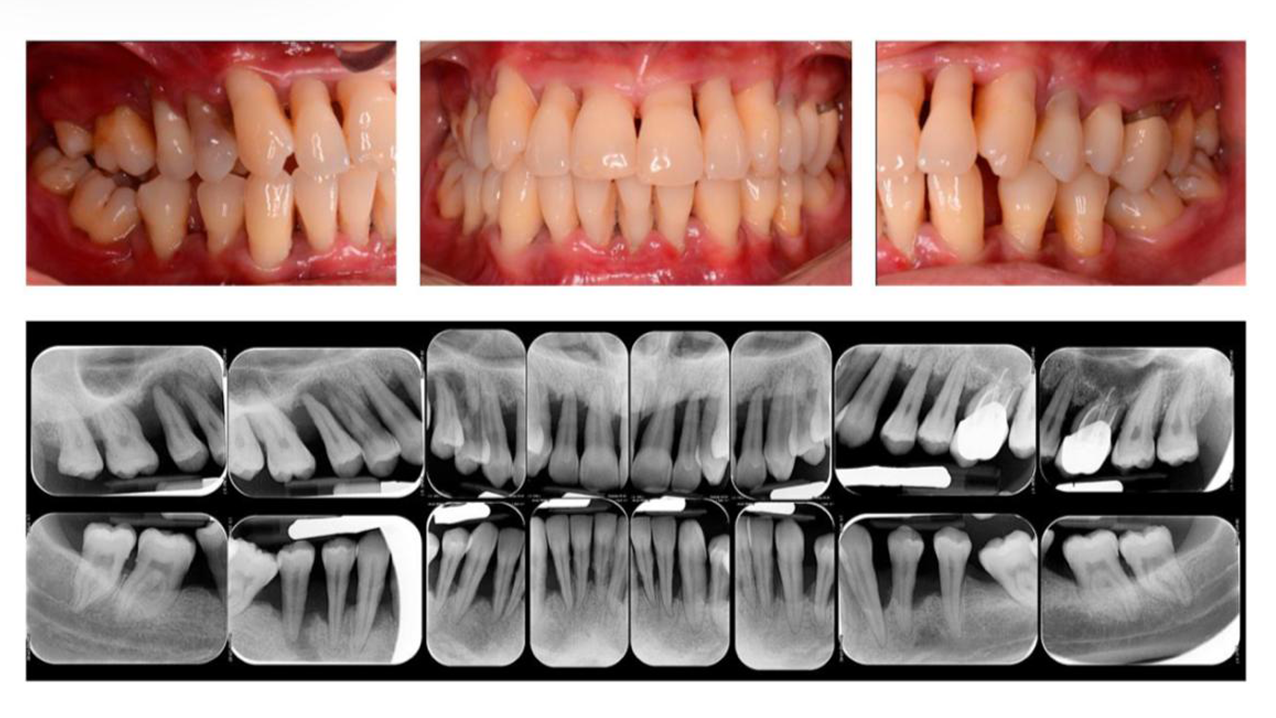

Penyakit periodontal merupakan kondisi peradangan kronis mengenai jaringan pendukung gigi yang meliputi gingiva, ligamentum periodontal, sementum, dan tulang alveolar.